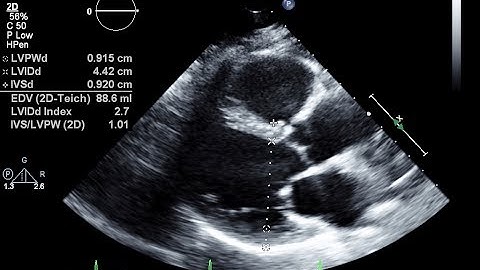

IAC and SDMS Present: Advanced Optimization of Your Echo Images and Doppler Evaluations